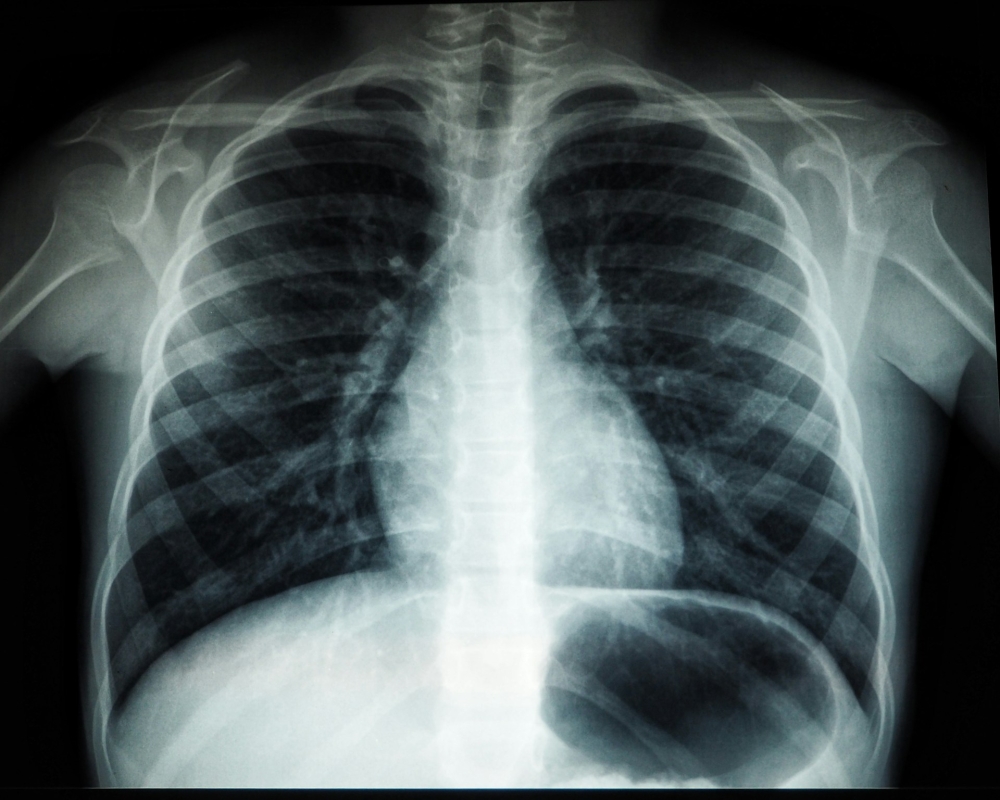

National Six schoolchildren quarantined after contracting tuberculosis in Kota Tinggi outbreak By Ben Tan - February 6, 2026 0 96 FacebookTwitterPinterestWhatsApp Most Read Life / 16 h ago Malaysia / 19 h ago Malaysia / 6 h ago Malaysia / 3 h ago Malaysia / 16 h ago Money / 16 h ago World / 6 h ago Money / 18 h ago World / 16 h ago Malaysia / 19 h ago Malaysia / 16 h ago Showbiz / 6 h ago Malaysia / 3 h ago Malaysia / 3 h ago Sports / 18 h ago You May Also Like Related Articles Malaysia / 1 m ago Malaysia / 15 m ago Malaysia / 32 m ago Just IN 1 m ago 15 m ago 32 m ago ↑